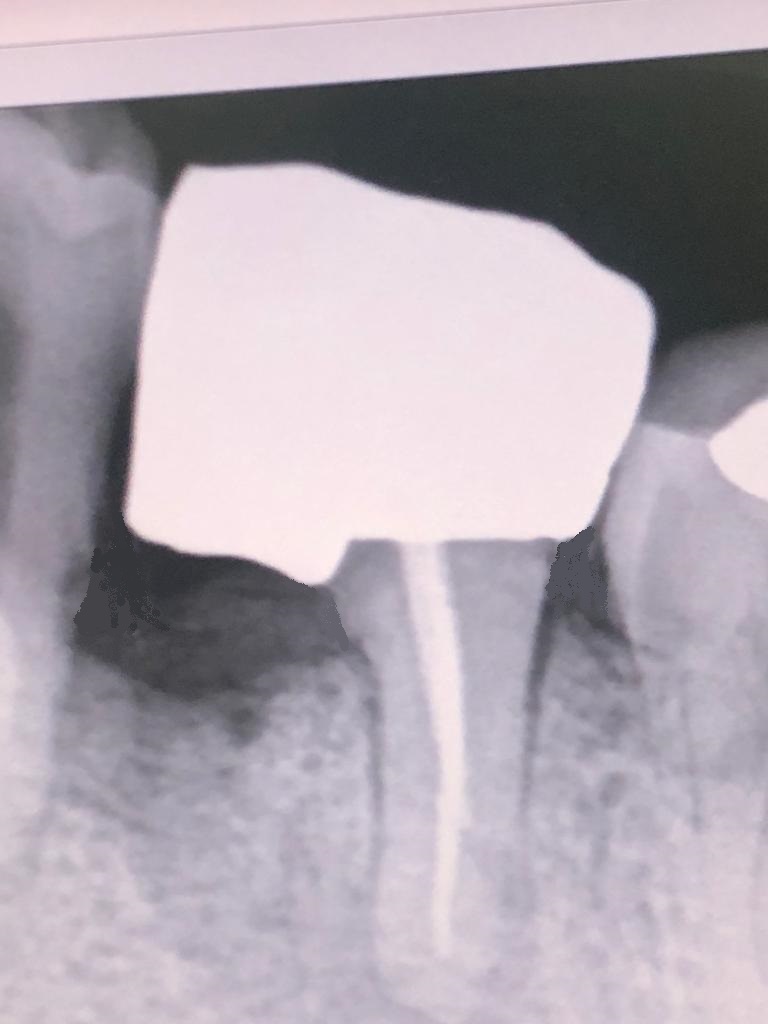

Pasado un tiempo se le cita para tallar el muñón de la raíz distal, que ha tenido una buena evolución una vez separada de la raíz anterior infectada.

En la misma sesión se le instala el hilo de retracción, para la toma de impresiones con siliconas. También diseñamos una corona de circonio multilayer, la cual se le cementa al cabo de una semana. Esta corona de circonio se deja muy suave de oclusión para que no sea presionada por las fuerzas de masticación y bruxismo, porque tendría más tendencia a la fractura.